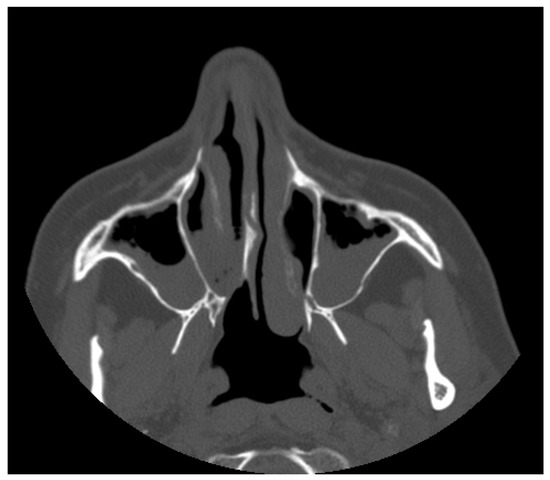

A 55-year-old female was observed due to significant breathing difficulties. After the completion of the rite of privacy and informed consent to the carrying out of investigations, the physical examination was performed by means of a Nasopharyngoscope XION Medical (Berlin, Germany) diameter of 4 mm previously disinfected, according to the regulations in force. The examination documented the presence of nasal polyposis bilaterally, confirmed by axial scan (Figure 1).

Figure 1. Axial scan of the facial massif where the polypoid formation is seen in both nostrils and maxillary sinuses.